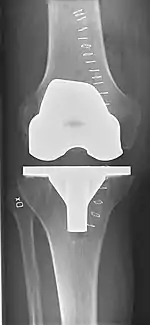

Knee replacement surgery can be performed as a partial or a total knee replacement.[3] In general, the surgery consists of replacing the diseased or damaged joint surfaces of the knee with metal and plastic components shaped to allow continued motion of the knee.

The surgery involves exposure of the front of the knee, with detachment of part of the quadriceps muscle (vastus medialis) from the patella. The patella is displaced to one side of the joint, allowing exposure of the distal end of the femur and the proximal end of the tibia. The ends of these bones then are cut accurately to shape, using cutting guides oriented to the long axis of the bones. The cartilages and the anterior cruciate ligament are removed; the posterior cruciate ligament also may be removed but the tibial and fibular collateral ligaments are preserved.[20] Whether the posterior cruciate ligament is removed or preserved depends on the type of implant used, although there appears to be no clear difference in knee function or range of motion favoring either approach.[20] Metal components are then impacted onto the bone or fixed using polymethylmethacrylate (PMMA) cement. Alternative techniques exist that affix the implant without cement. These cement-less techniques may involve osseointegration, including porous metal prostheses. Finally, stability and range of motion are checked, followed by irrigation, hemostasis, placement of hemovacs, and closure.[21]

Femoral replacement

A round-ended implant is used for the femur, mimicking the natural shape of the joint. On the tibia the component is flat, although it sometimes has a stem that goes down inside the bone for further stability. A flattened or slightly dished high-density polyethylene surface is then inserted onto the tibial component so the weight is transferred metal to plastic, not metal to metal. During the operation any deformities must be corrected, and the ligaments balanced so the knee has a good range of movement, and is stable and aligned. In some cases the articular surface of the patella also is removed and replaced by a polyethylene button cemented to the posterior surface of the patella. In other cases, the patella is replaced unaltered.